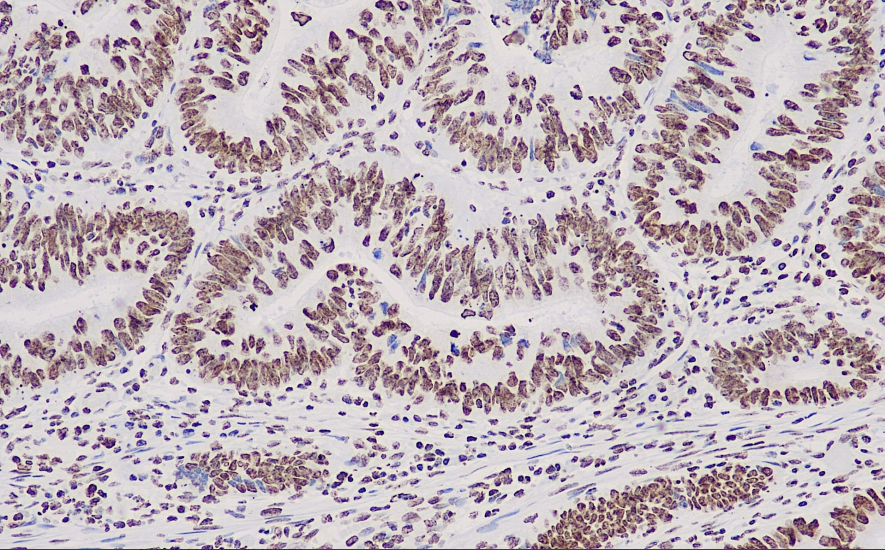

阳性对照: 结直肠癌

ERCC1是核苷酸切除修复通路中高度保守的切除性核酶,是有效修复烷化剂诱导的DNA复合物的必要条件。目前初步的研究表明,肿瘤中的ERCC1蛋白表达程度越低,顺氯氨铂化疗的效果就越好。ERCC1蛋白阳性的患者,非化疗治疗的预后要好于接受化疗。

ERCC1抗体试剂可与ERCC1分子抗原特异性结合,含ERCC1抗体试剂的免疫组化试剂盒适用于预测铂类化疗(如顺铂)耐药性(如肺癌、卵巢癌)。